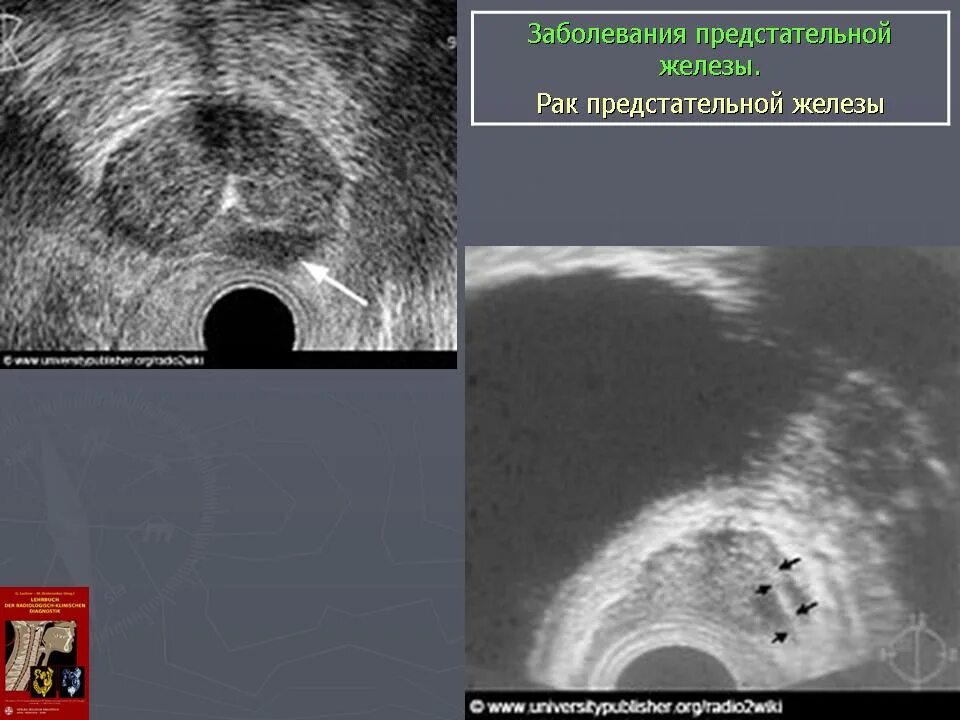

Предстательная железа у мужчин. Представительна яжелеза. Опухальпредседательнойжелезы Трансректальное УЗИ предстательной железы. УЗИ трузи предстательной железы. Карцинома предстательной железы УЗИ. Опухоль предстательной железы УЗИ

Трансректальное УЗИ предстательной железы. УЗИ трузи предстательной железы. Карцинома предстательной железы УЗИ. Опухоль предстательной железы УЗИ Массажер для аденомы простаты. Массаж предстательной железы мужчинам

Образование предстательной железы УЗИ. УЗИ предстательной железы РПЖ. Диагностика опухолей предстательной железы

Образование предстательной железы УЗИ. УЗИ предстательной железы РПЖ. Диагностика опухолей предстательной железы Злокачественное новообразование предстательной железы. Онкозаболевания предстательной железы. Аденома простаты злокачественная. Мкб предстательной железы